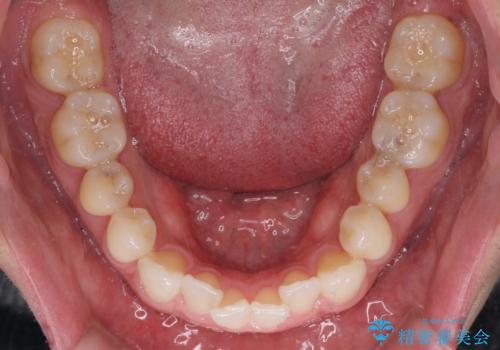

- 上下前歯の叢生を気にして来院された患者様です。

費用を抑え、期間もあまりかけずに治療をしたいとのことで、インビザライン・ライトを用いて矯正治療を行うこととしました。

インビザライン・ライトは、製作できるアライナーの枚数に制限があるため、移動可能な量に限りがあります。

一方で、半年から1年程度で治療を終えることができるため、軽度の歯列不正の患者様には大変お勧めです。